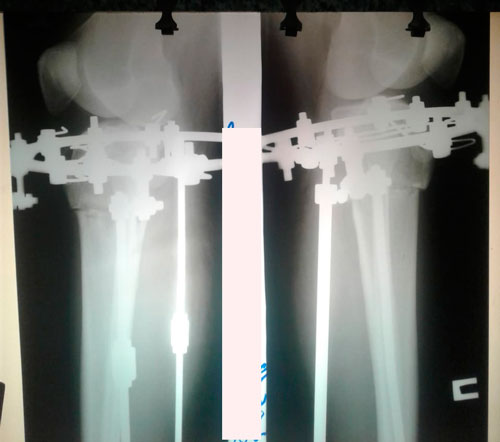

Исходник - 35 лет.

Ротация с обеих сторон.

Дата операции - 08.04.2019г.